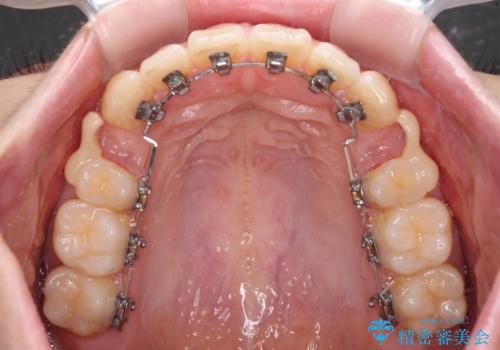

- ハーフリンガル

上下前歯が嘴のように前方に突出しており、唇が閉じにくい状態であったため、上下左右の第一小臼歯4本を抜歯して、口元の突出感を改善することとしました。

目立たない装置を希望とのことで、上顎が裏側、下顎が表側のハーフリンガル装置を用いることとしました。